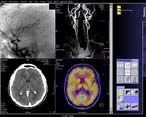

В ноябре 2002 года в Бобруйском межрайонном онкологическом диспансере начал работать спиральный компьютерный томограф SOMATOM Esprit+ фирмы SIEMENS. На 2 декабря было обследовано 22 пациента.

EspritКак видно, аппарат, о котором пойдет речь, относится к семейству SOMATOM Emotion. За 2 года с начала выпуска установлено более 1000 аппаратов этого семейства в 60 странах мира, причем 20% из них находятся в США. Естественно, что все перечисленные томографы являются спиральными, т. к. технология последовательного (неспирального сканирования) не отвечает современным требованиям объемного сканирования (volume scanning).

Основные технические характеристики спиральных компьютерных томографов SOMATOM Esprit & Esprit+ представлены в таблице.

Параметры Esprit Esprit+

Число одновременно сканирующих спиралей 1 4

Время полного оборота блока трубка-детекторы 1,5 сек 1,0 сек

Максимальная длительность спирали 40 сек 60 сек

Минимальная ширина среза 1,5 мм 1 мм

Максимальная мощность генератора 22 кВ 24 кВ

Емкость накопителя (изображений) 13000 13000

Время реконструкции (матрица 512х512) 2 сек 2 сек

Для сравнения приводим параметры установленного в начале года в Институте онкологии компьютерного томографа SOMATOM Volume Zoom:

Параметры Esprit+ Volume Zoom

Время полного оборота блока трубка-детекторы 1,0 сек 0,5 сек

Минимальная ширина среза 1,5 мм 0,5 мм

EspritДля инсталляции SOMATOM Esprit+ необходимо лишь 17 м2. Используемый в нем UFC (Ultra-Fast Ceramic) детектор (как и в Volume Zoom) позволяет снизить дозу на 30%. Программа CARE (Combined Applications to Reduce Exposure) еще более снижает облучение пациента, персонала (например, при интервенционных процедурах) и расход контрастного вещества. Апертура гентри составляет 65 см, максимальный вес пациента 200 кг, минимальная высота стола 45 см, гентри наклоняется до ±25°. Особая конструкция гентри с плавно закругляющимися к центру краями практически исключает клаустрафобию. Емкость диска основного компьютера - 18 ГБ, что достаточно для 13000 изображений и 2750 сырых данных. Информация сохраняется на внешние носители: CD-R 0,7 ГБ и MOD 2,3 или 4,1 ГБ.

Топограмма отображается в реальном времени на экране монитора, имеется возможность в любой момент остановить движение стола и соответственно сканирование. Максимальная длина топограммы - 1024 см. Максимальная длина зоны сканирования - 120 см.

syngoВсе томографы фирмы SIEMENS объединяет единый интерфейс пользователя - syngo. Помимо стандартных закладок Examination, Viewing, Filming имеется закладка 3D с возможностями осуществлений MPR- (в реальном времени) и MIP-реконструкций. Програмно и технически (в комплект поставки вошел автоматический инъектор Medrad CT Tripak CTP-200-FLS) реализованы возможности КТ-ангиографии. Имеется опциональная программа Pulmo CT для исследования легочной эмфиземы.